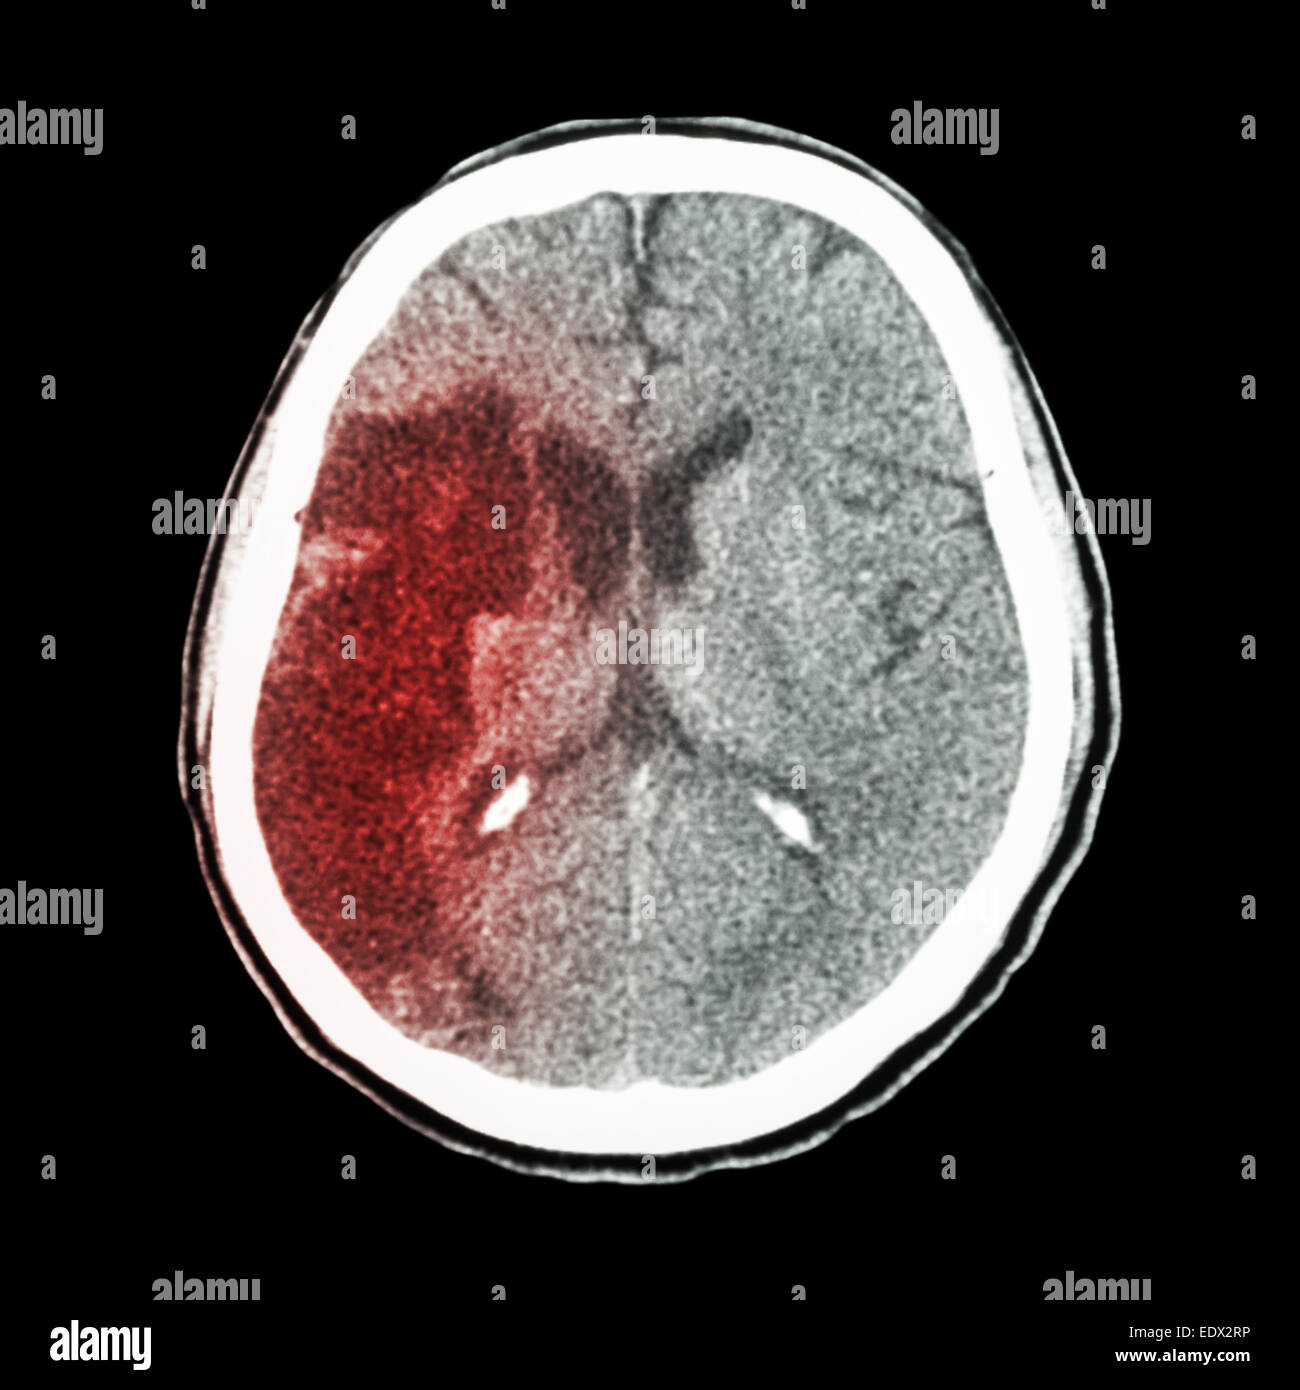

Scanographie du cerveau d'un homme de 73 ans montrent une hémorragie intracrânienne Banque D'Imageshttps://www.alamyimages.fr/image-license-details/?v=1https://www.alamyimages.fr/photo-image-scanographie-du-cerveau-d-un-homme-de-73-ans-montrent-une-hemorragie-intracranienne-25635131.html

Scanographie du cerveau d'un homme de 73 ans montrent une hémorragie intracrânienne Banque D'Imageshttps://www.alamyimages.fr/image-license-details/?v=1https://www.alamyimages.fr/photo-image-scanographie-du-cerveau-d-un-homme-de-73-ans-montrent-une-hemorragie-intracranienne-25635131.htmlRMBDKNTB–Scanographie du cerveau d'un homme de 73 ans montrent une hémorragie intracrânienne

Scanographie du cerveau d'un homme de 73 ans montrent une hémorragie intracrânienne Banque D'Imageshttps://www.alamyimages.fr/image-license-details/?v=1https://www.alamyimages.fr/photo-image-scanographie-du-cerveau-d-un-homme-de-73-ans-montrent-une-hemorragie-intracranienne-25635128.html

Scanographie du cerveau d'un homme de 73 ans montrent une hémorragie intracrânienne Banque D'Imageshttps://www.alamyimages.fr/image-license-details/?v=1https://www.alamyimages.fr/photo-image-scanographie-du-cerveau-d-un-homme-de-73-ans-montrent-une-hemorragie-intracranienne-25635128.htmlRMBDKNT8–Scanographie du cerveau d'un homme de 73 ans montrent une hémorragie intracrânienne